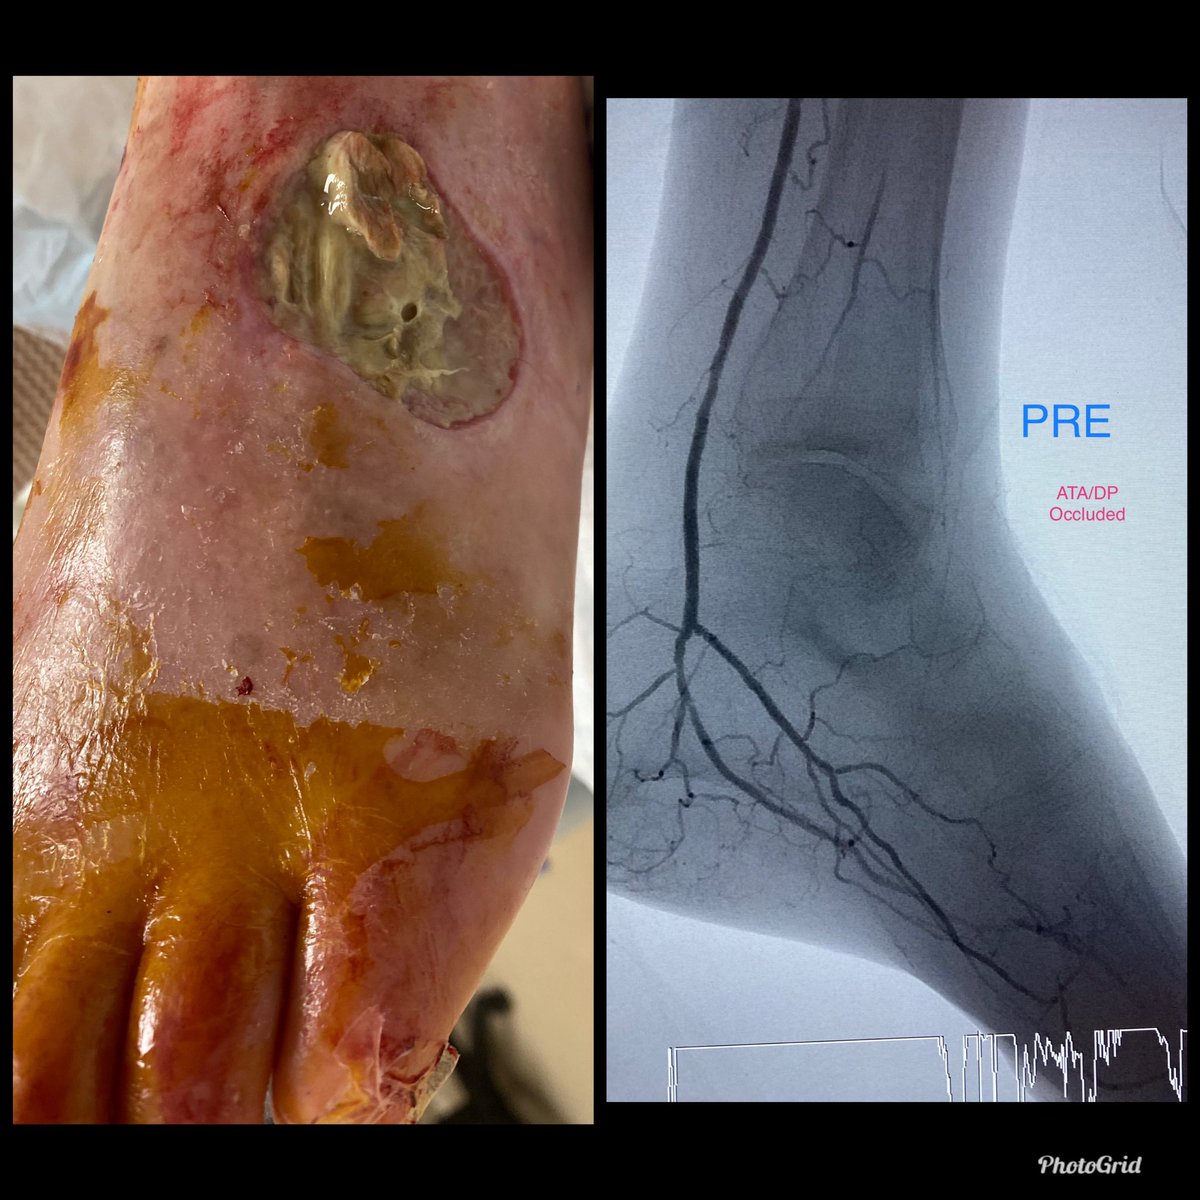

Dorsal foot wound, stent jailing origin of occluded AT, unable to retrograde puncture occluded AT. Pedal loop retrograde traversal of occluded AT to localize its origin followed by antegrade traversal of stent interstices, balloon, stent

@SoFloVIR@OmoKinju@SIRRFSpic.twitter.com/P2QFYbHgG7